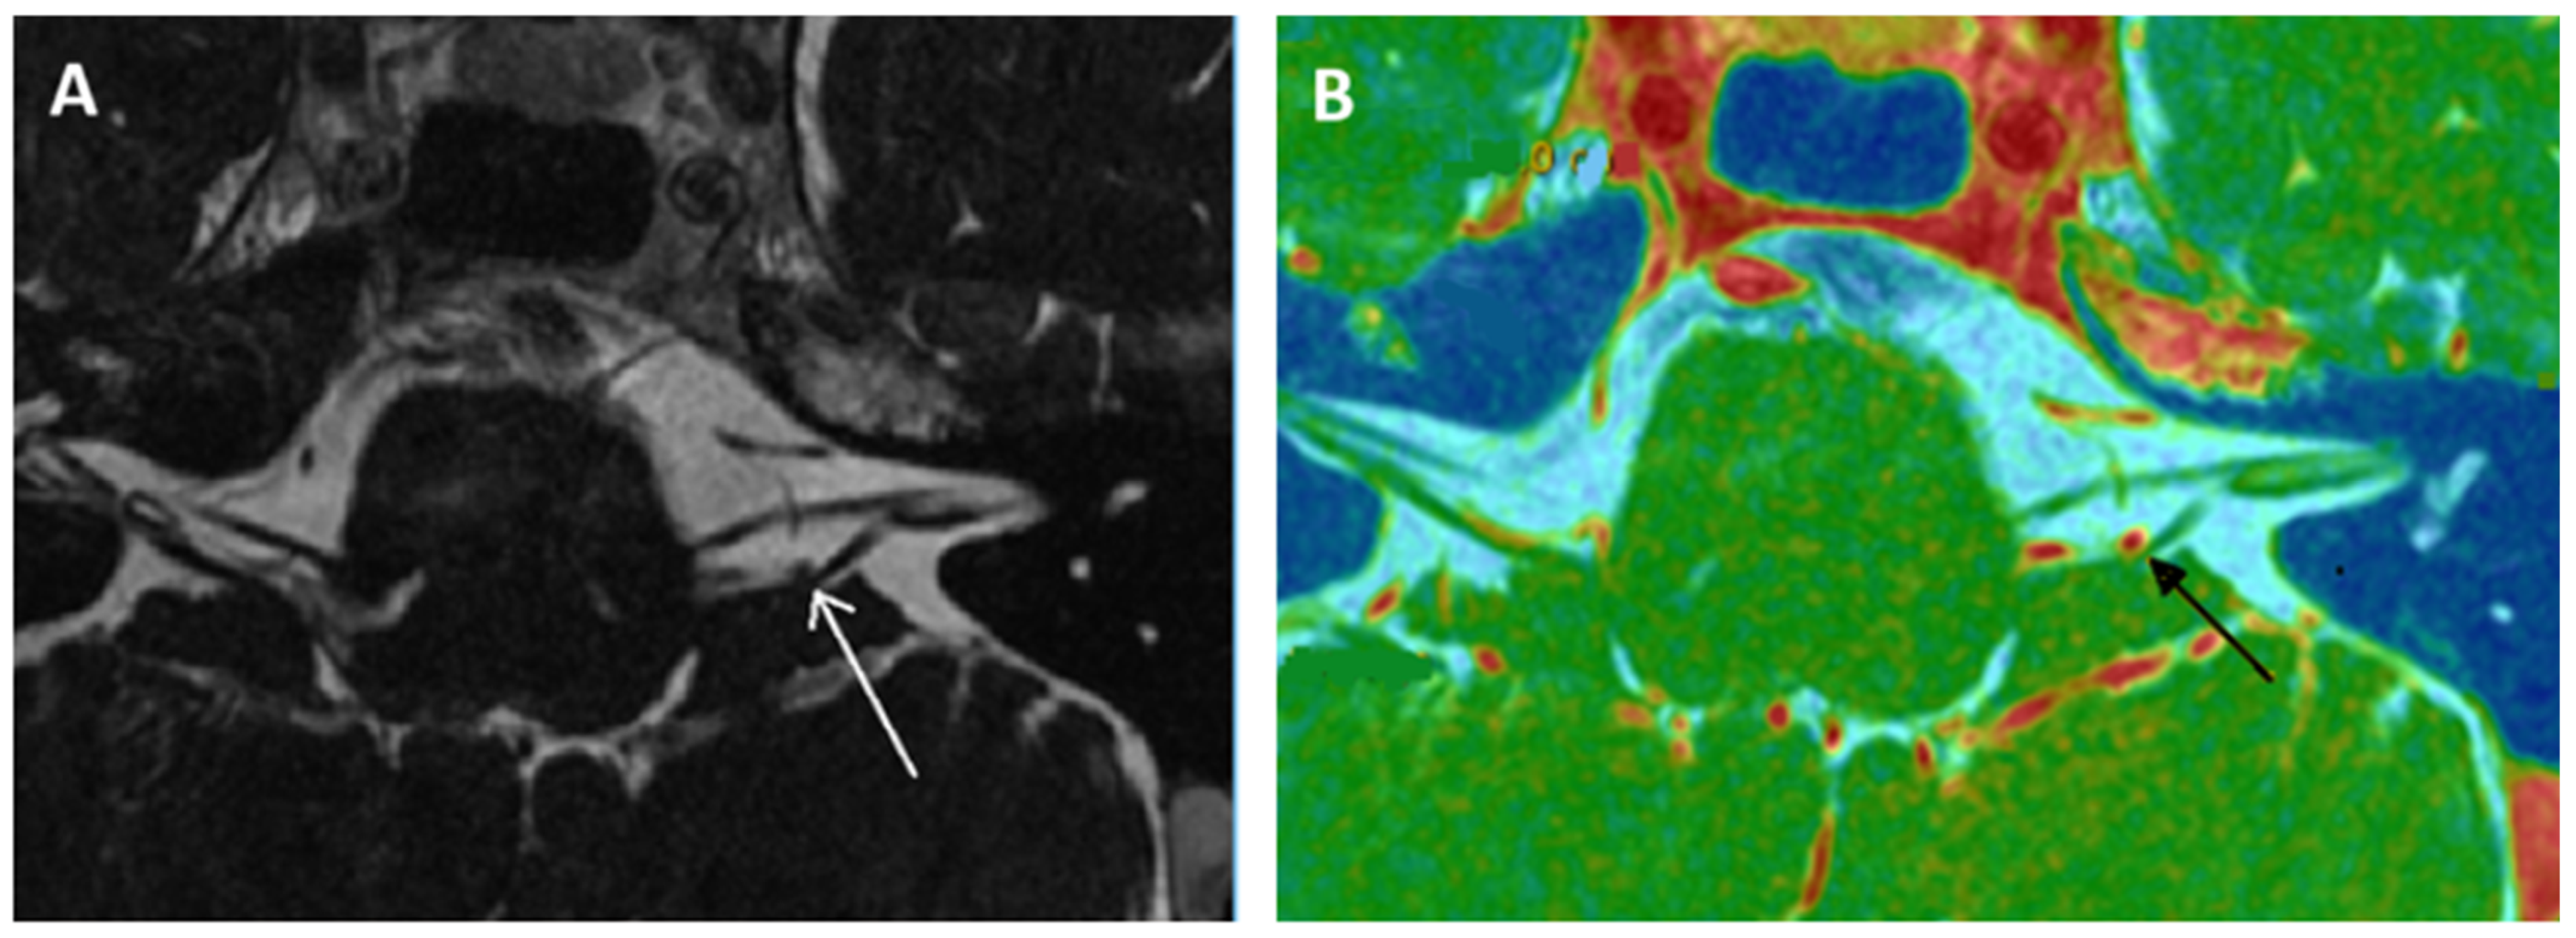

- Kierig, E.; Gerb, J.; Boegle, R.; Ertl-Wagner, B.; Dieterich, M.; Kirsch, V. Vestibular paroxysmia entails vestibular nerve function, microstructure and endolymphatic space changes linked to root-entry zone neurovascular compression. J. Neurol. 2023, 270, 82–100. [Google Scholar] [CrossRef] [PubMed]